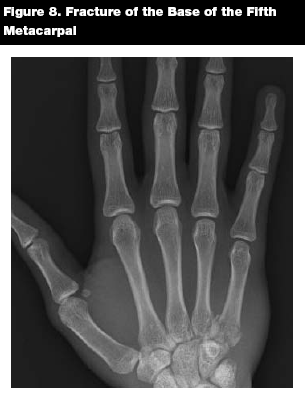

Metacarpal base fractures are uncommon and often require ORIF due to joint involvement. (See Figure 8.) If there is no joint involvement, closed reduction may be performed. Five percent angulation is tolerated in the first two fingers; in the ring and little fingers, 15% angulation is allowed.22 Appropriate consultation and referral are indicated.

![]() |